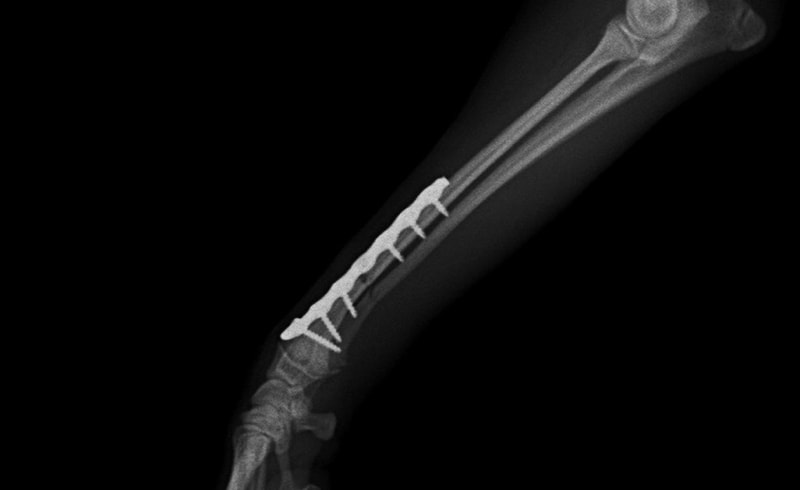

トイプードル 右遠位橈尺骨短斜骨折のALPSによる内固定

Locking Compression Plate

LCPは、スクリュー(ネジ)とプレート(金属の板)をロックする特殊な構造により骨折部位を固定する新しい世代のプレートシステムです。ひとつのホールでロッキングスクリューとスタンダードスクリューの使用を選択できるユニークな構造をしているため、骨折断端間の圧迫を目的とした従来型プレート固定法に加え、高い角度安定性を有するロッキングスクリューを用いた固定法の選択が可能です。従来のプレートシステムでは困難だった部分の骨折や癒合不全の症例に高い治療効果をもたらします。